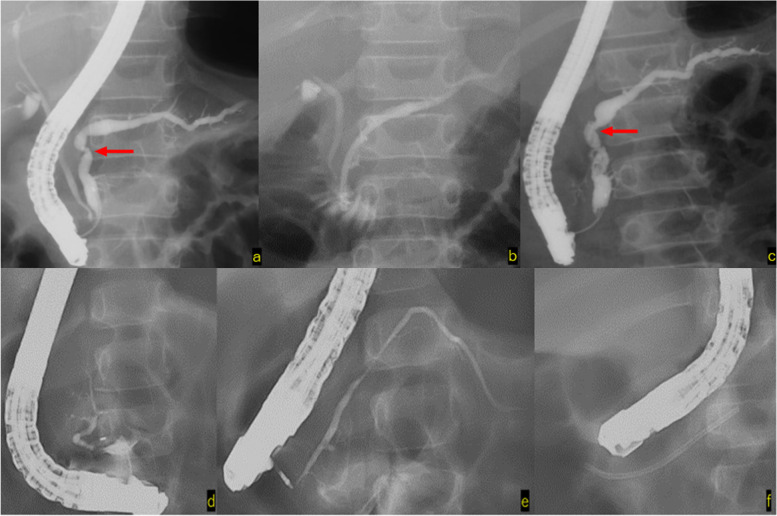

All three patients with chronic pancreatitis had diffuse dilatation and wide irregularities involving the pancreatic duct, and pancreatic duct stents were emplaced. EPS was performed repeatedly; however, all patients eventually underwent pancreatic stent removal and were followed up without recurrence of pancreatitis (Fig. 5).

In Case 5, ERCP was performed 6 times, and the stenosis of the pancreatic duct was alleviated by placing a stent. No recurrence of pancreatitis has been observed for 14 years and 5 months after stent removal (Fig. 5a, b and c).

Pancreatic divisum and Others

Of two patients with pancreas divisum, it was difficult to insert a stent into the accessory papilla in Case 8 and only contrast imaging was performed; the patient is currently being followed-up on an outpatient basis. In Case 9, a pancreatic duct stent was placed from the accessory papilla to the caudal pancreatic duct, and the patient was confirmed to have no symptoms of pancreatitis, after which endocscopic minor papilla shincterotomy was performed. Fifteen months have passed since the endocscopic minor papilla shincterotomy was performed; however, no recurrence of symptoms has been observed (Fig. 5d, e and f).